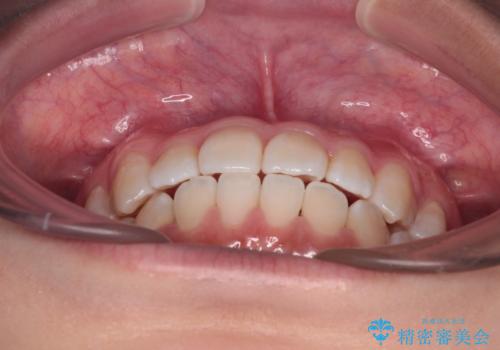

- 前歯のデコボコを治したいとのことで来院された患者様です。

インビザラインによるマウスピース矯正も適用となる歯列でしたが、できる限り楽して、短期間で治したいとのことで、ワイヤー装置にて矯正治療を行うこととしました。